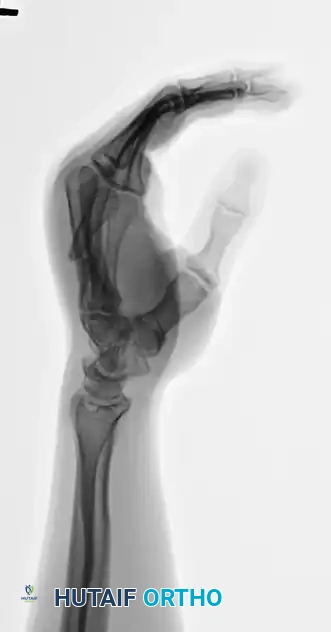

Review the preoperative deformity carefully to understand the required reduction vectors.

FIGURE 67-35A: Preoperative AP radiograph of a fifth metacarpal neck fracture.

FIGURE 67-35B: Preoperative oblique radiograph demonstrating displacement.

FIGURE 67-35C: Preoperative lateral radiograph showing 80-degree apex dorsal angulation and rotational deformity.